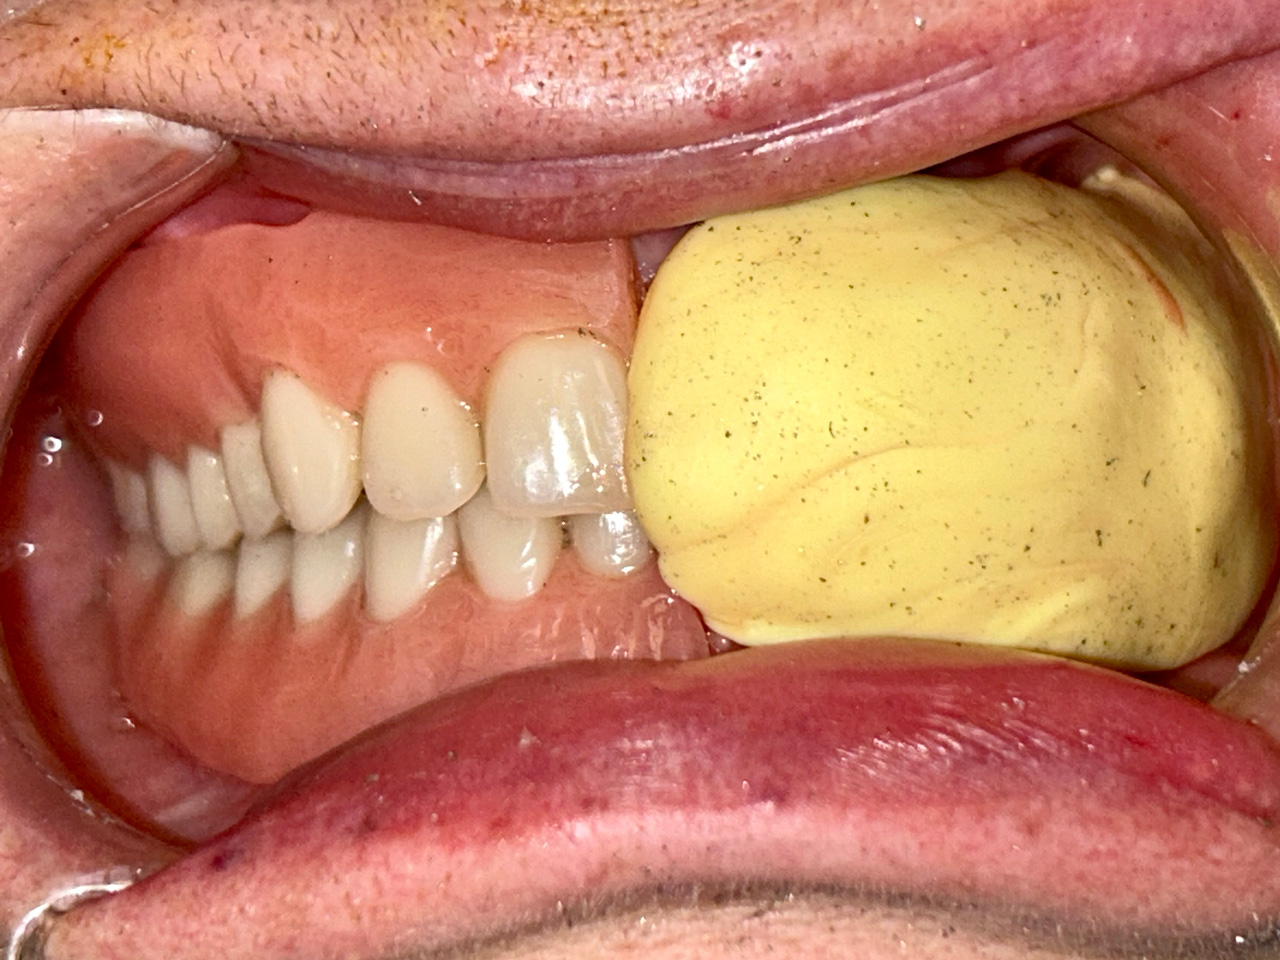

Alsó állcsont teljes rehabilitációja 72 óra alatt

Alsó állcsont teljes rehabilitációja 72 óra alatt, azonnal terhelhető implantátumokkal súlyos paradontitisben szenvedő dohányzó páciens esetében. Az alsó állcsont fogai mind mozogtak az előrehaladott fogágypusztulás miatt.

A fogakat eltávolítottuk, a gyulladt, fertőzött csontot kitakarítottuk, kifertőtlenítettük, majd azonnal implantáltunk.

Svájci, IHDE márkájú, azonnal terhelhető implantátumokat helyzetünk be, és ezekre harmadnapra rögzített, hosszútávú, fémvázas, esztétikus műanyaggal leplezett hidat ragasztottunk be.

Ezt az ideiglenes hidat a sebek gyógyulása miatt használjuk, de tartóssága miatt véglegesként is használható. A legtöbb esetben, ahogy itt is, 6 hónap múlva porcelán hídra cseréljük, a teljes gyógyulás után.